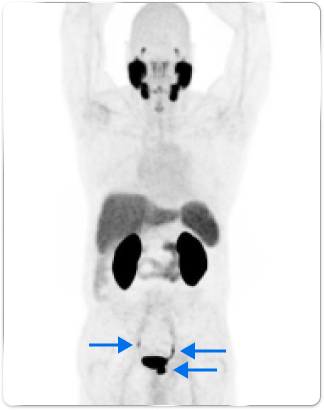

High-risk patient with newly diagnosed prostate cancer

Age

63

PSA (ng/mL)

26

Gleason Score

4 + 3

PYLARIFY may have helped prevent overtreatment